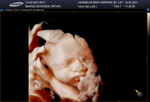

#CeritaKehamilanTAP Pengalaman hamil anak pertama.. Setelah nikah sy langsung promil salah satunya dengan minum susu prenagen esensis dan pola hidup sehat pastinya.. Sy hamil setelah 1 bulan menikah, Alhamdulillah Allah SWT langsung memberi amanah. Mulai kontrol setiap bulan diklinik dekat rumah, merasakan mual, pegal dan mudah lelah. Tapi masih bisa diajak mengajar si baby gemoynya.. Perkembangannya juga selalu baik. Usg usia 34 minggu ternyata ada 1 lilitan dileher dan bayi cenderung besar karena beratnya sudah 3,2kg padahal tubuh ibunya kurus loh hehe. Tetep kasih aura positif ke si baby sambil dikasih tau biar bisa lahiran normal dan sehat tanpa kurang apapun. Dan tidak diduga" usia kehamilan jalan 38 minggu selesai sahur udah rembes air ketuban dan flek. Suami panik tapi saya tetap tenang sambil ngukir alis dan pakai lipstik hehe Langsung cus ke puskesmas, sampai sana sudah pembukaan 2 dan tanpa mules plus ketuban yang makin deres. Saya gak panik malah nekat kekamar mandi jalan sendiri.. krn dri awal mendekati bulan kelahiran saya sudah ikhlas apapun prosesnya, dinikmatin dan tetap rileks.. Akhirnya sy dirujuk ke rsia terdekat dan harus tindakan SC krn pinggul sempit bayinya besar. Okee yang penting ibu dan si baby gemoy sehat dan semua lancar.. Alhamdulillah lahir bayi laki laki yang gemesin dan sekarang sudah usia 3 bulan. Happy, bersyukur dan nikmat rasanya menjadi orang tua.. Begitu lah cerita singkat kehamilan saya. Pesan untuk bumil yang mendekati hpl Jangan panik. Rileks dan serahkan semuanya sama tuhan yang terbaik. Nikmatin semua prosesnya dan bersyukur sudah diberikan amanah menjadi seorang ibu.. #stayhealty #stayathome #hamilpertama #bersyukur #nikmatin #babygemoy